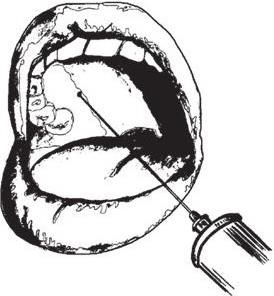

Внутриротовой доступ: при полуоткрытом рте зубоврачебным зеркалом отводят в сторону щеку, обеспечивая достаточный обзор свода преддверия рта и натяжение слизистой оболочки переходной складки в области моляров. Иглу вкалывают в слизистую оболочку выше проекции верхушек зубов на уровне второго-третьего моляров, а при их отсутствии – позади скулоальвеолярного гребня, вводя ее под углом 45° и продвигая вверх, назад и внутрь. При этом нужно следить за тем, чтобы игла все время скользила скошенной поверхностью острия по кости. По ходу продвижения иглы следует медленно выпускать раствор анестетика, предупреждая тем самым повреждение кровеносных сосудов крыловидного сплетения. Продвигая иглу на глубину 2 – 2,5 см, депонируют раствор анестезирующего вещества, чем достигается обезболивание области моляров, прилежащих к ним со стороны преддверия рта слизистой оболочки и надкостницы, а также задненаружной костной стенки верхнечелюстной пазухи (рис. 1.1, а). Внеротовой доступ: проколов кожу у передненижнего угла скуловой кости, направляют иглу под углом 45° вверх и внутрь к бугру верхней челюсти, доводя ее до кости; после чего депонируют раствор анестетика. Время наступления анестезии в зоне обезболивания такое же, как и при анестезии внутриротовым доступом (см. рис. 1.1, б).

Рис. 1.1. Анестезия на бугре верхней челюсти:

а – внутриротовой доступ; б – внеротовой доступ